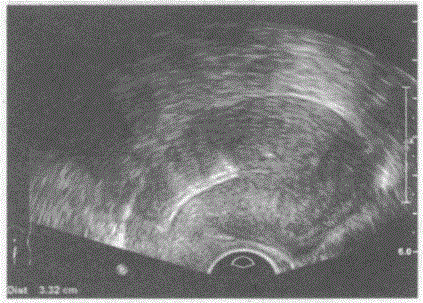

问题 临床资料:女,30岁,自诉放置节育器5年,腹部不适。 超声综合描述:经阴道扫查子宫后位,形态大小正常,肌壁回声均匀,宫腔内可见"-"字形强回声,距宫底3.2cm。 超声提示:

选项 A.宫腔内气体回声 B.异位节育器 C.宫内节育器位置正常 D.宫内节育器位置下移

答案 D